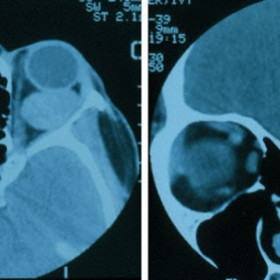

Retinoblastoma

Retinoblastoma - Computed radiographic tomography demonstrates calcium (arrow) within a large intraocular retinoblastoma

Retinoblastoma - Computed radiographic tomography (CT) demonstrates unilateral buphthalmos and bilateral intraocular calcifications.